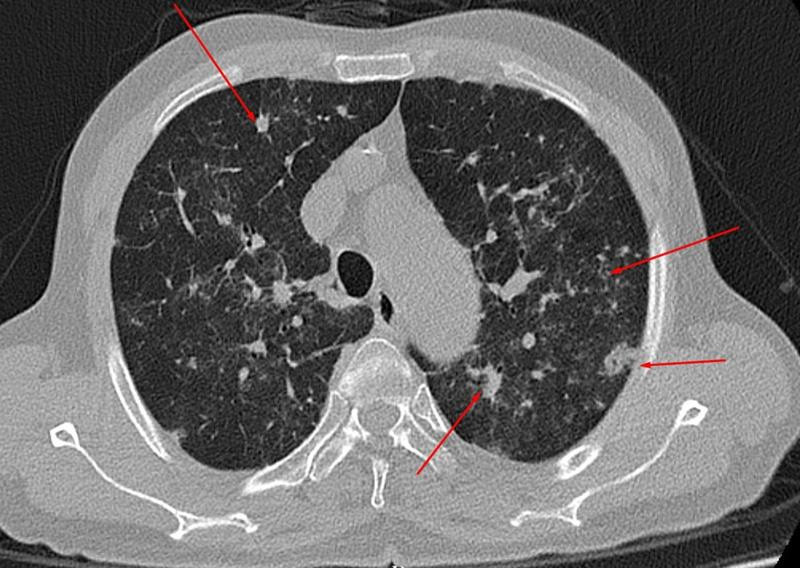

Hình ảnh chụp CT lồng ngực của bệnh nhân sau khi khỏi Covid-19. (Ảnh: BVCC)

Sau khi tới khám hậu COVID-19 tại một bệnh viện ở Phú Thọ, ông nhận kết quả chụp CT lồng ngực cho hình ảnh phổi đông đặc, tổn thương lan tỏa 2 bên.

Trước đó, người đàn ông này cho biết trong thời gian mắc COVID-19 chỉ có các triệu chứng nhẹ, khỏi bệnh nhanh. Tuy nhiên, di chứng hậu COVID-19 ở phổi của trường hợp này rất nặng.